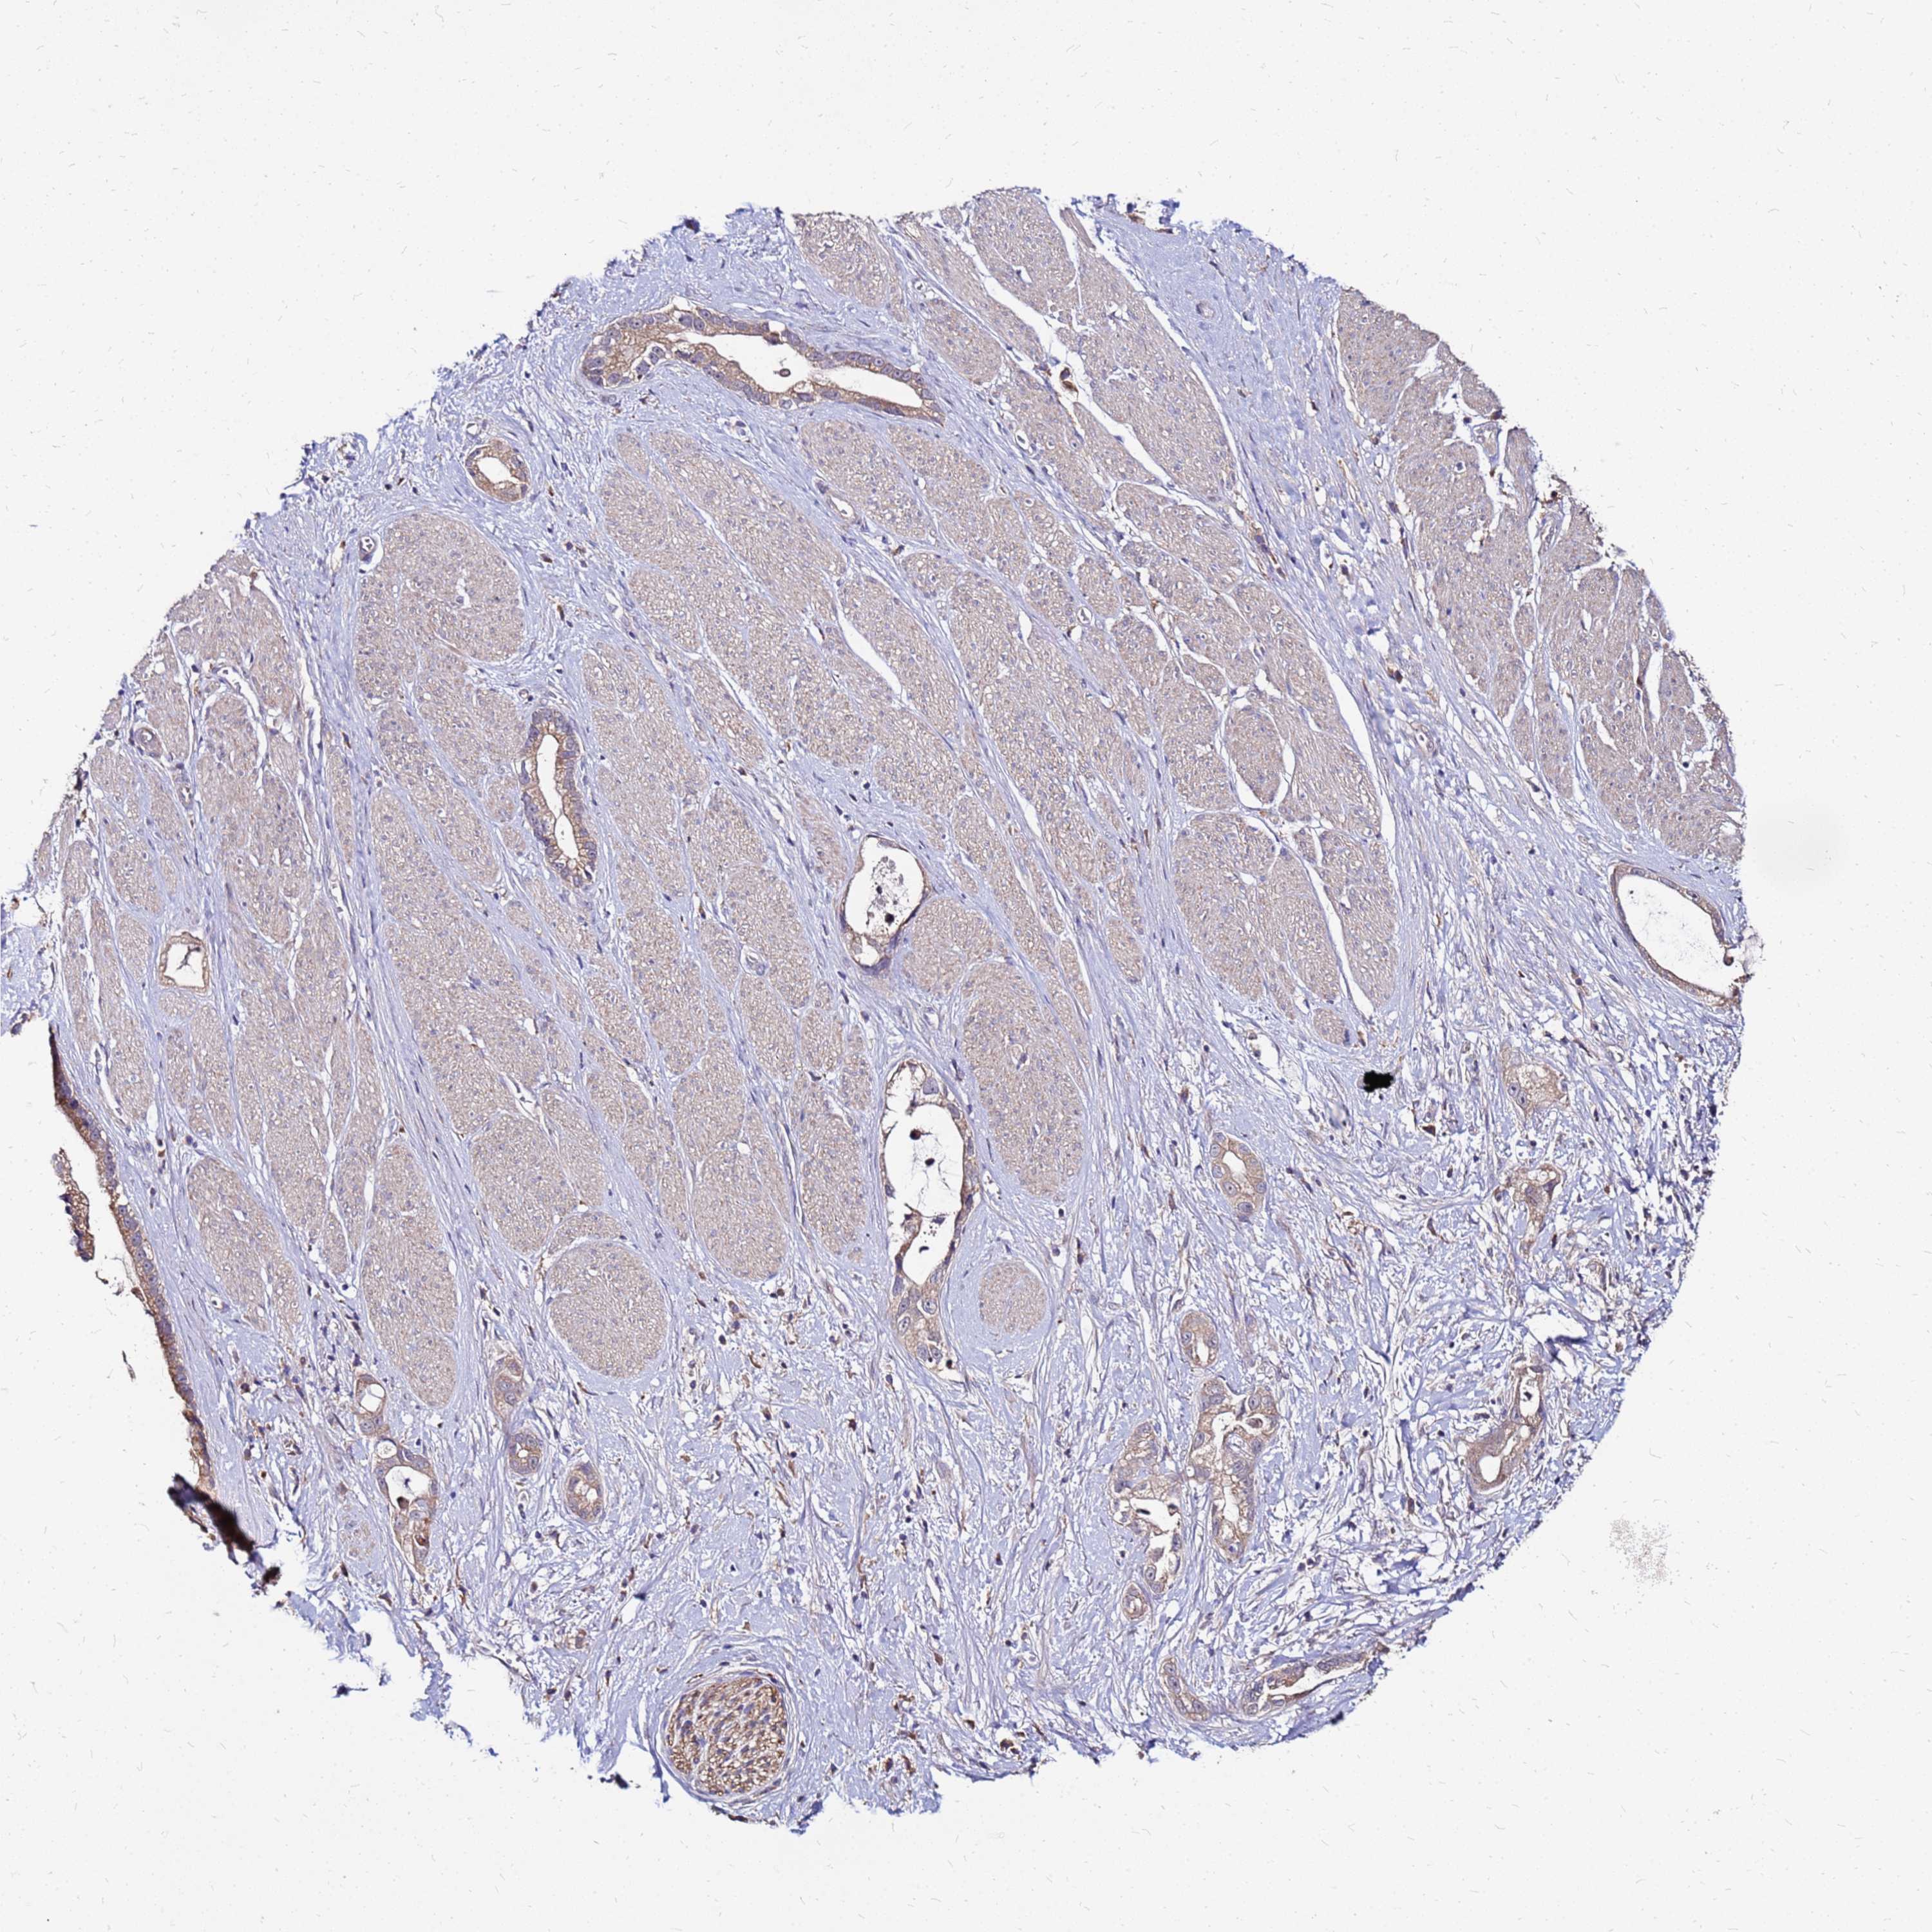

STOMACH CANCER - Protein expressioni

A mouse-over function shows sample information and annotation data. Click on an image to view it in a full screen mode. Samples can be filtered based on level of antibody staining by selecting one or several of the following categories: high, medium, low and not detected. The assay and annotation is described here.

Note that samples used for immunohistochemistry by the Human Protein Atlas do not correspond to samples in the TCGA dataset.

Antibody stainingi

Antibody staining in the annotated cell types in the current human tissue is reported as not detected, low, medium, or high, based on conventional immunohistochemistry profiling in selected tissues. This score is based on the combination of the staining intensity and fraction of stained cells.

Each image is clickable and will lead to virtual microscopy that enables deeper exploration of all samples and also displays staining intensity scores, fraction scores and subcellular localization as well as patient and tissue information for each sample.

Antibody HPA044188

Antibody HPA045619

Antibody HPA045699

Staining

High

Medium

Low

Not detected

Intensity

Strong

Moderate

Weak

Negative

Quantity

>75%

75%-25%

<25%

None

Location

Nuclear

Cytoplasmic/membranous

Cytoplasmic/membranous,nuclear

Adenocarcinoma, NOS